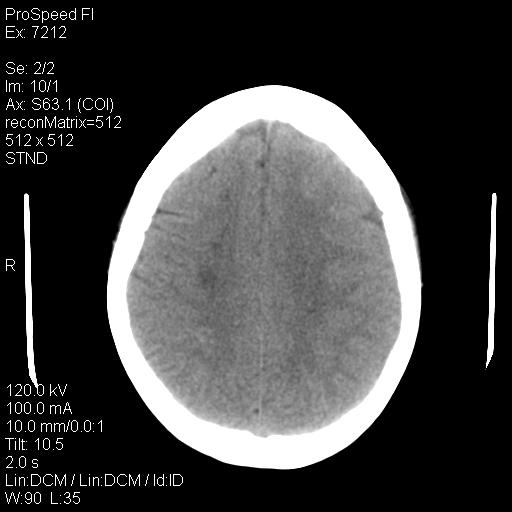

右额叶脑沟变浅,脑表面见新月形稍高密度影,考虑慢性硬膜下出血可能。

1)考虑左侧额颞部及右侧额部慢性硬膜下血肿(或硬膜下积液)。2)颅骨骨髓瘤不排除;建议行进一步检查。

考虑左侧额部慢性硬膜下血肿(或硬膜下积液)。

1)考虑左侧额部慢性硬膜下血肿(或硬膜下积液)。2)颅骨骨髓瘤不排除;建议行进一步检查。

1)右侧半卵圆中心腔隙性脑梗塞。2)考虑左侧额部慢性硬膜下血肿(或硬膜下积液)。3)颅骨骨髓瘤不排除;建议行进一步检查。